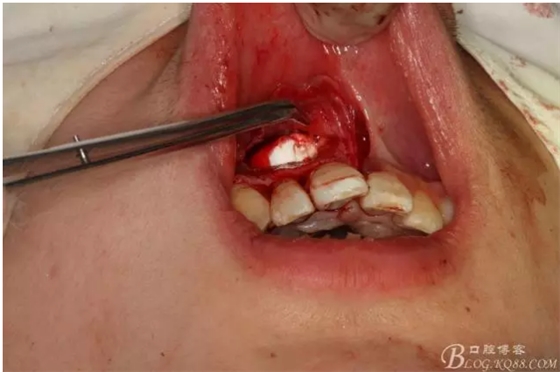

圖5.清理骨腔,可以看到12的根尖暴露在骨腔內。

圖6.超聲骨刀切除根尖3mm。